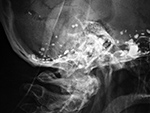

Pantopaque in the base of the cranium |

Residual Pantopaque in the base of the cranium from a myelogram performed with Pantopaque many years prior. From Hunter, 1994 |